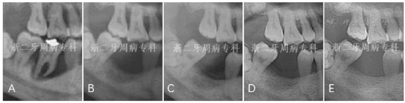

全口曲面体层X片示:全口牙槽骨广泛性水平吸收,46牙槽骨吸收超过根尖;36根尖周和根分叉区低密度影;13、22、23、33~35、43~45、47牙槽骨吸收达根长1/2~2/3,余牙牙槽骨吸收至近根尖(图3)。